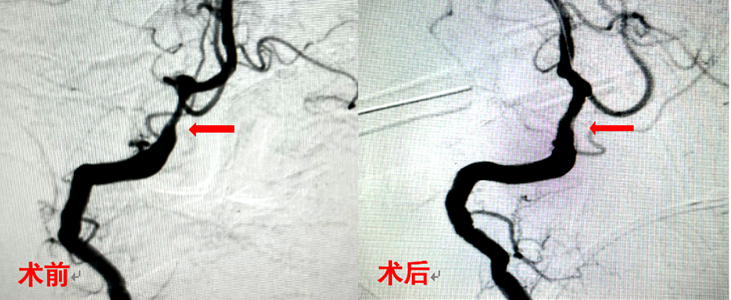

病例1:女,77岁,因“头晕伴视物旋转1个月”就诊,脑血管造影发现“左侧椎动脉闭塞,右侧椎动脉V4段狭窄”,行右侧椎动脉支架置入术,术后造影显示原狭窄处血管开通良好,患者头晕症状明显缓解。